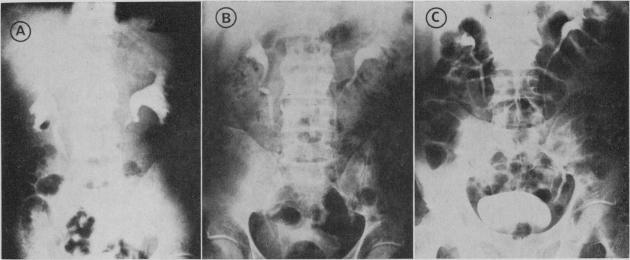

A 40-year-old carpenter presented with vomiting due to duodenal obstruction. On further investigation he had partial obstruction of both ureters and occlusion of the inferior vena cava. At laparotomy a large retroperitoneal mass of fibrous tissue was found, which extended into the root of the mesentery of the small intestine and partially occluded the duodenum. There was enlargement of lymphatics and stasis of lymph throughout the mesentery. Hypoalbuminemia was present. (131)I-labelled human serum albumin disappeared rapidly from the plasma and there was excessive loss of plasma albumin into the gastrointestinal tract, presumably owing to obstruction of the lymphatic drainage of the small intestine. Prompt improvement followed treatment with prednisolone. Steroids are apparently useful in this condition, early in the disease before irreversible fibrosis has developed. The presenting feature, vomiting due to duodenal obstruction, has been reported in retroperitoneal fibrosis only once before. This is the first report of protein-losing enteropathy in this disorder.

一名40岁的木匠因十二指肠梗阻出现呕吐症状。进一步检查发现他双侧输尿管部分梗阻,下腔静脉闭塞。剖腹手术时发现一个巨大的腹膜后纤维组织肿块,延伸至小肠系膜根部并部分阻塞十二指肠。整个系膜淋巴管扩张,淋巴淤滞。存在低白蛋白血症。(131)I标记的人血清白蛋白从血浆中迅速消失,血浆白蛋白大量丢失到胃肠道,推测是由于小肠淋巴引流受阻。泼尼松龙治疗后症状迅速改善。在这种疾病中,在不可逆纤维化形成之前的早期阶段,类固醇显然是有用的。因十二指肠梗阻导致呕吐这一表现特征,此前仅在腹膜后纤维化中报道过一次。这是关于这种疾病中蛋白丢失性肠病的首次报告。